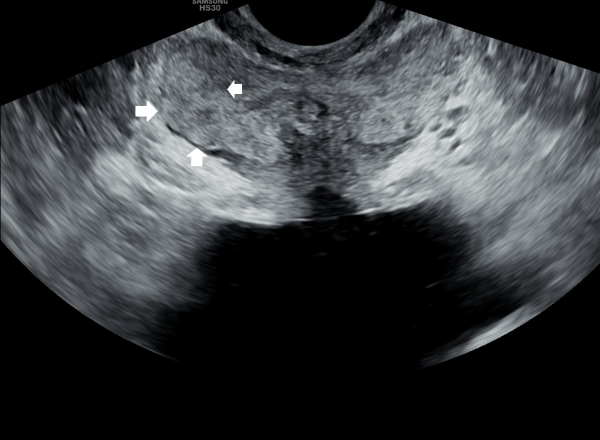

서울가정의학과의원에 첫 내원 당일 지난 5개월동안 회음부 통증과 배뇨장애로 타 비뇨기과 여러곳에서 치료를 했으나 증상의 호전이 없다고 내원 당일 검사한 경직장 전립선 초음파 검사상 사정관 입구의 석회화와 사정관의 섬유화 그리고 정낭의 낭종이 관찰되는 초음파 자료입니다.

On the first visit to Seoul Family Medicine Clinic, the patient reported having perineal pain and urination problems for the past five months, despite receiving treatment at several other urology clinics with no improvement.

A transrectal prostate ultrasound performed on the day of the visit showed calcification at the opening of the ejaculatory duct, fibrosis (scarring) of the duct itself, and cysts in the seminal vesicles.

또한 방광벽이 배뇨장애로 두꺼워져 과민성 방광이 의심되는 초음파 사진입니다.

The ultrasound image also shows that the bladder wall has become thickened, likely due to urination difficulties. This may suggest an overactive bladder, which can cause frequent or urgent urination.

내원 당일 경직장 전립선 초음파 검사상 오랜 세월동안 사정관의 벽이 수명을 다한 거짓 중층 원주 상피 세포가 탈락되어 사정관 입구에 막혀 두텁게 쌓여 있고 요도에도 탈락된 상피 세포가 쌓여서 정낭과 정관 그리고 전립선액 과 배뇨등의 순환 장애를 보이고 있는 경직장 전립선 초음파 사진입니다.

This transrectal prostate ultrasound image, taken on your first visit, shows that over many years, the wall of the ejaculatory duct has been blocked by a buildup of old, shed pseudostratified columnar epithelial cells. These cells have accumulated at the opening of the ejaculatory duct and in the urethra, leading to circulation problems in the seminal vesicles, vas deferens, and prostate fluid, as well as urinary flow issues.